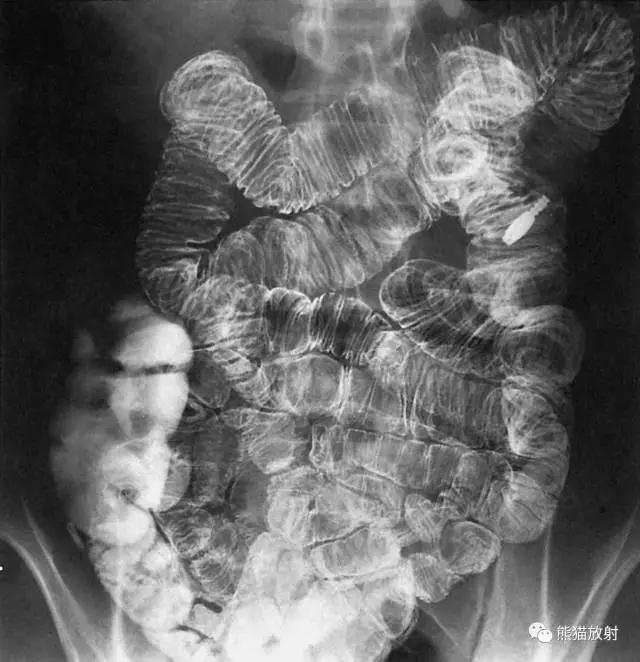

8 Small Bowel 小肠

1 Jejunum 空肠,2 Junction of the ileum and jejunum 回肠和空肠的连接部,3 Ileum 回肠,4 Cecum 盲肠,5 Appendix 阑尾